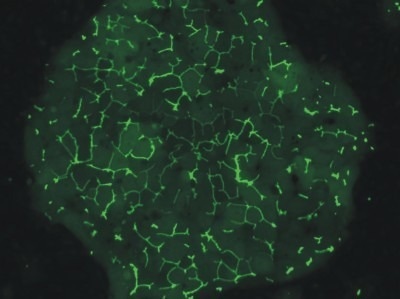

Morphology

Human HEPATOPAC cultures were developed and sustained in a laboratory setting for a period exceeding four weeks. Throughout this period, there were no significant changes to the morphology of micropatterned cultures and the polygonal shape was maintained. The movement of a fluorescent dye through MRP-2 evidenced the strong connectivity of bile canaliculi among the hepatocytes.

Image Credit: BioIVT